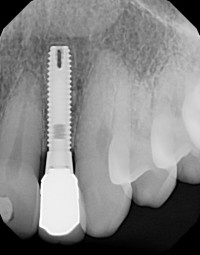

Biomet 3i

Miniplant

Connection Interface

Internal interface

Body Shape

Non-tapered body

Thread Design

ThreadedV-shaped threads

Additional Features

Flared flangeFlat apeximplantOblong holeWider flange